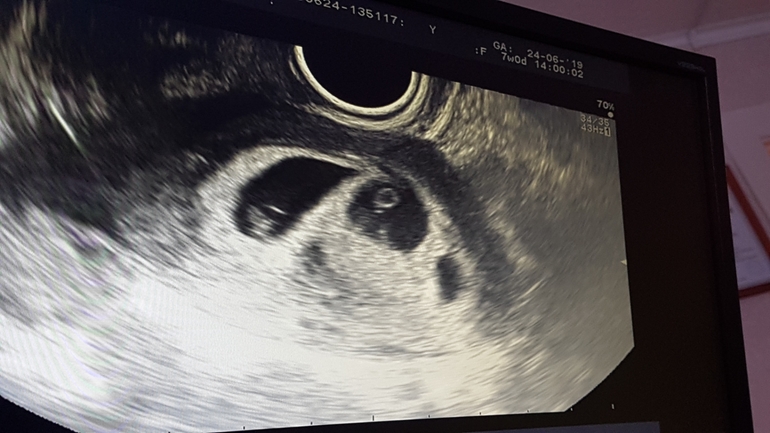

Двойня или тройня?

2. От 2.07.2020

фото прилагаю

Врач сказала , что это не развивающиеся ПЯ, но вот в чем проблема откуда он взялся ???

у меня также 1 узи 2пя, потом 3 пя, но э только в 2х.

скрининг в 12 нед.3 пя было, в 16 нед уже не было видно.

Неделю назад два пя были, как третье сегодня... возможно, разные даты оплодотворения. Либо рассосется, если пустое, либо третий. Делайте ещё через неделю